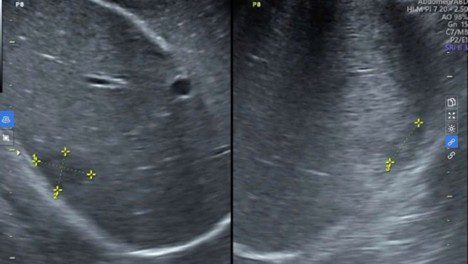

Hình ảnh siêu âm của bệnh nhân.

Kết quả của bệnh nhân cho thấy bệnh nhân có chỉ số bạch cầu ái toan tăng cao, trong máu có kháng thể IgG của sán lá gan lớn, siêu âm ổ bụng phát hiện 1 khối ở gan kích thước 39x18x20mm giới hạn không rõ, không bắt tín hiệu doppler, nằm sát vỏ bao gan, không xô đẩy các cấu trúc xung quanh. Kết quả CT phù hợp với hình ảnh tổn thương gan do ký sinh trùng (sán lá gan).

Từ kết quả khai thác các yếu tố dịch tễ, khám lâm sàng và xét nghiệm, bác sĩ Lệ kết luận bệnh nhân bị áp xe gan do sán lá gan lớn ở hạ phân thùy VII, kích thước 20x39mm, giai đoạn ổn định, không biến chứng vỡ.

Sau 1 tháng điều trị, chị V. giảm đau bụng vùng thượng vị, BCAT trở về bình thường, ổ tổn thương ở gan giảm kích thước rõ rệt trên siêu âm. Đồng thời, chị V. được bác sĩ BS Lệ tư vấn tái khám, làm các xét nghiệm để theo dõi kết quả điều trị.